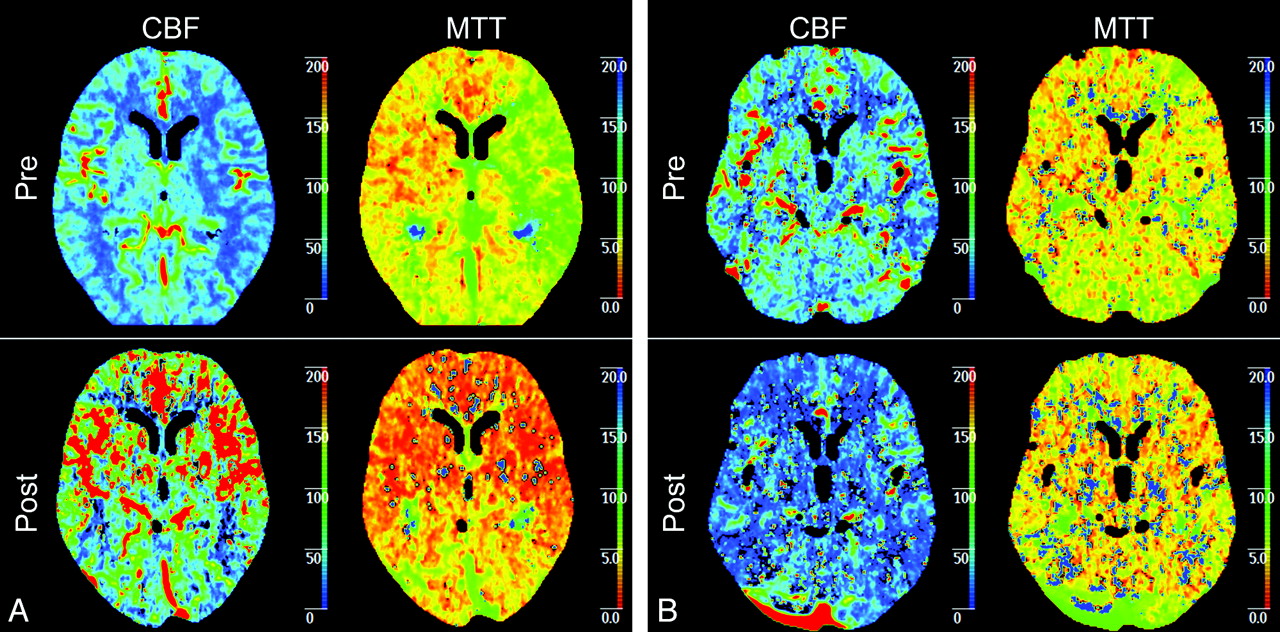

The purpose of this study was to compare how cerebral perfusion is affected by CAS in patients with symptomatic and asymptomatic carotid artery stenosis. First, our results showed a significant improvement after CAS of all 3 perfusion parameters in symptomatic patients, while in asymptomatic patients, only rCBF showed a significant increase. So despite the small number of patients in our study, both symptomatic and asymptomatic patients showed significant improvement of cerebral perfusion parameters after stent placement (Fig 3). When we compared symptomatic and asymptomatic patients before stent placement, rCBF was significantly lower in symptomatic patients. This indicates the presence of more hemodynamic compromise in these patients before treatment of carotid artery stenosis. Finally, rCBV after stent placement was significantly lower in symptomatic patients. In these patients, the compensatory hyperemia on the symptomatic side before treatment (rCBV > 1) turned into hypoxemia after treatment, suggesting impaired autoregulation. These differences in perfusion parameters between both groups of patients before and after stent placement are suggestive of the existence of a different hemodynamic status in symptomatic and asymptomatic patients.

A, Example of symptomatic patient with a left-sided carotid artery stenosis of 99%. Before treatment, CBF and MTT show explicit differences between the right and left hemispheres with a higher CBF and a higher MTT in the right hemisphere in comparison with the left hemisphere. After CAS, both CBF and MTT show a symmetric pattern of perfusion. B, An example of a asymptomatic patient with a left-sided carotid artery stenosis of 95%. Before treatment, CBF and MTT show differences between the right and left hemisphere with a higher CBF and a higher MTT in the right hemisphere in comparison with the left hemisphere. However, this difference is not as clear as in the symptomatic patient. After CAS, both CBF and MTT show a symmetric pattern of perfusion.